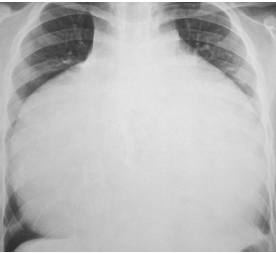

Um escolar de 10 anos tem história de cansaço aos esforços, que vem piorando progressivamente, e palpitações. Ao exame físico há hepatomegalia importante, turgência jugular e saturação de O2 de 89%. A ausculta cardíaca revela um sopro sistólico em borda paraesternal esquerda baixa. O eletrocardiograma mostra ondas P amplas e intervalo PR prolongado.

A radiografia de tórax está reproduzida abaixo.

Assinale a opção que mostra o diagnóstico mais provável.